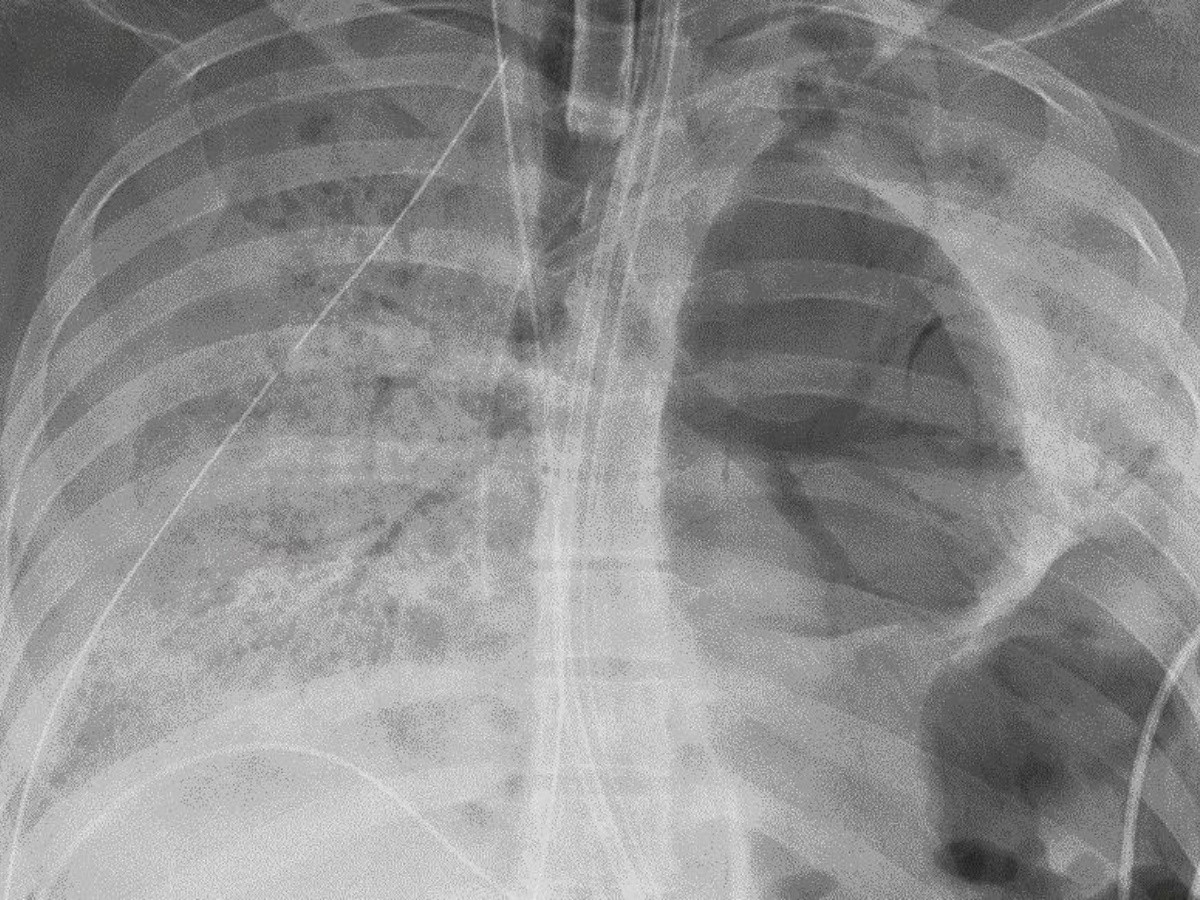

Los pulmones de un paciente que superó el Covid-19 y falleció por otra causa salvaron la vida de un hombre que sufrió daño permanente a causa del SARS-CoV-2 en Estados Unidos.

Cirujanos del Northwestern Medicine, encabezados por el médico Ankit Bharat, realizaron exitosamente un trasplante de doble pulmón a un hombre de Illinois de alrededor de 50 años.

El receptor padeció Covid-19 en mayo de 2020 y las secuelas que dejó la enfermedad no tenían cura, incluso lo obligaban a vivir conectado a un ventilador para poder respirar de forma artificial debido al daño pulmonar.

Tras una espera en la lista de trasplantes, el paciente recibió los pulmones. Lo extraordinario del caso es que se trata de uno de los primeros en el que el órgano es de un donante que fue caso confirmado de coronavirus.

Antes de realizar la cirugía se realizaron los análisis pertinentes para garantizar que el virus ya no se encontraba en el organismo.

A cinco meses de la operación, el paciente receptor ha mostrado una gran mejoría y no ha rechazado sus nuevos órganos a pesar de ser uno de los trasplantes más raros por ser de doble pulmón.